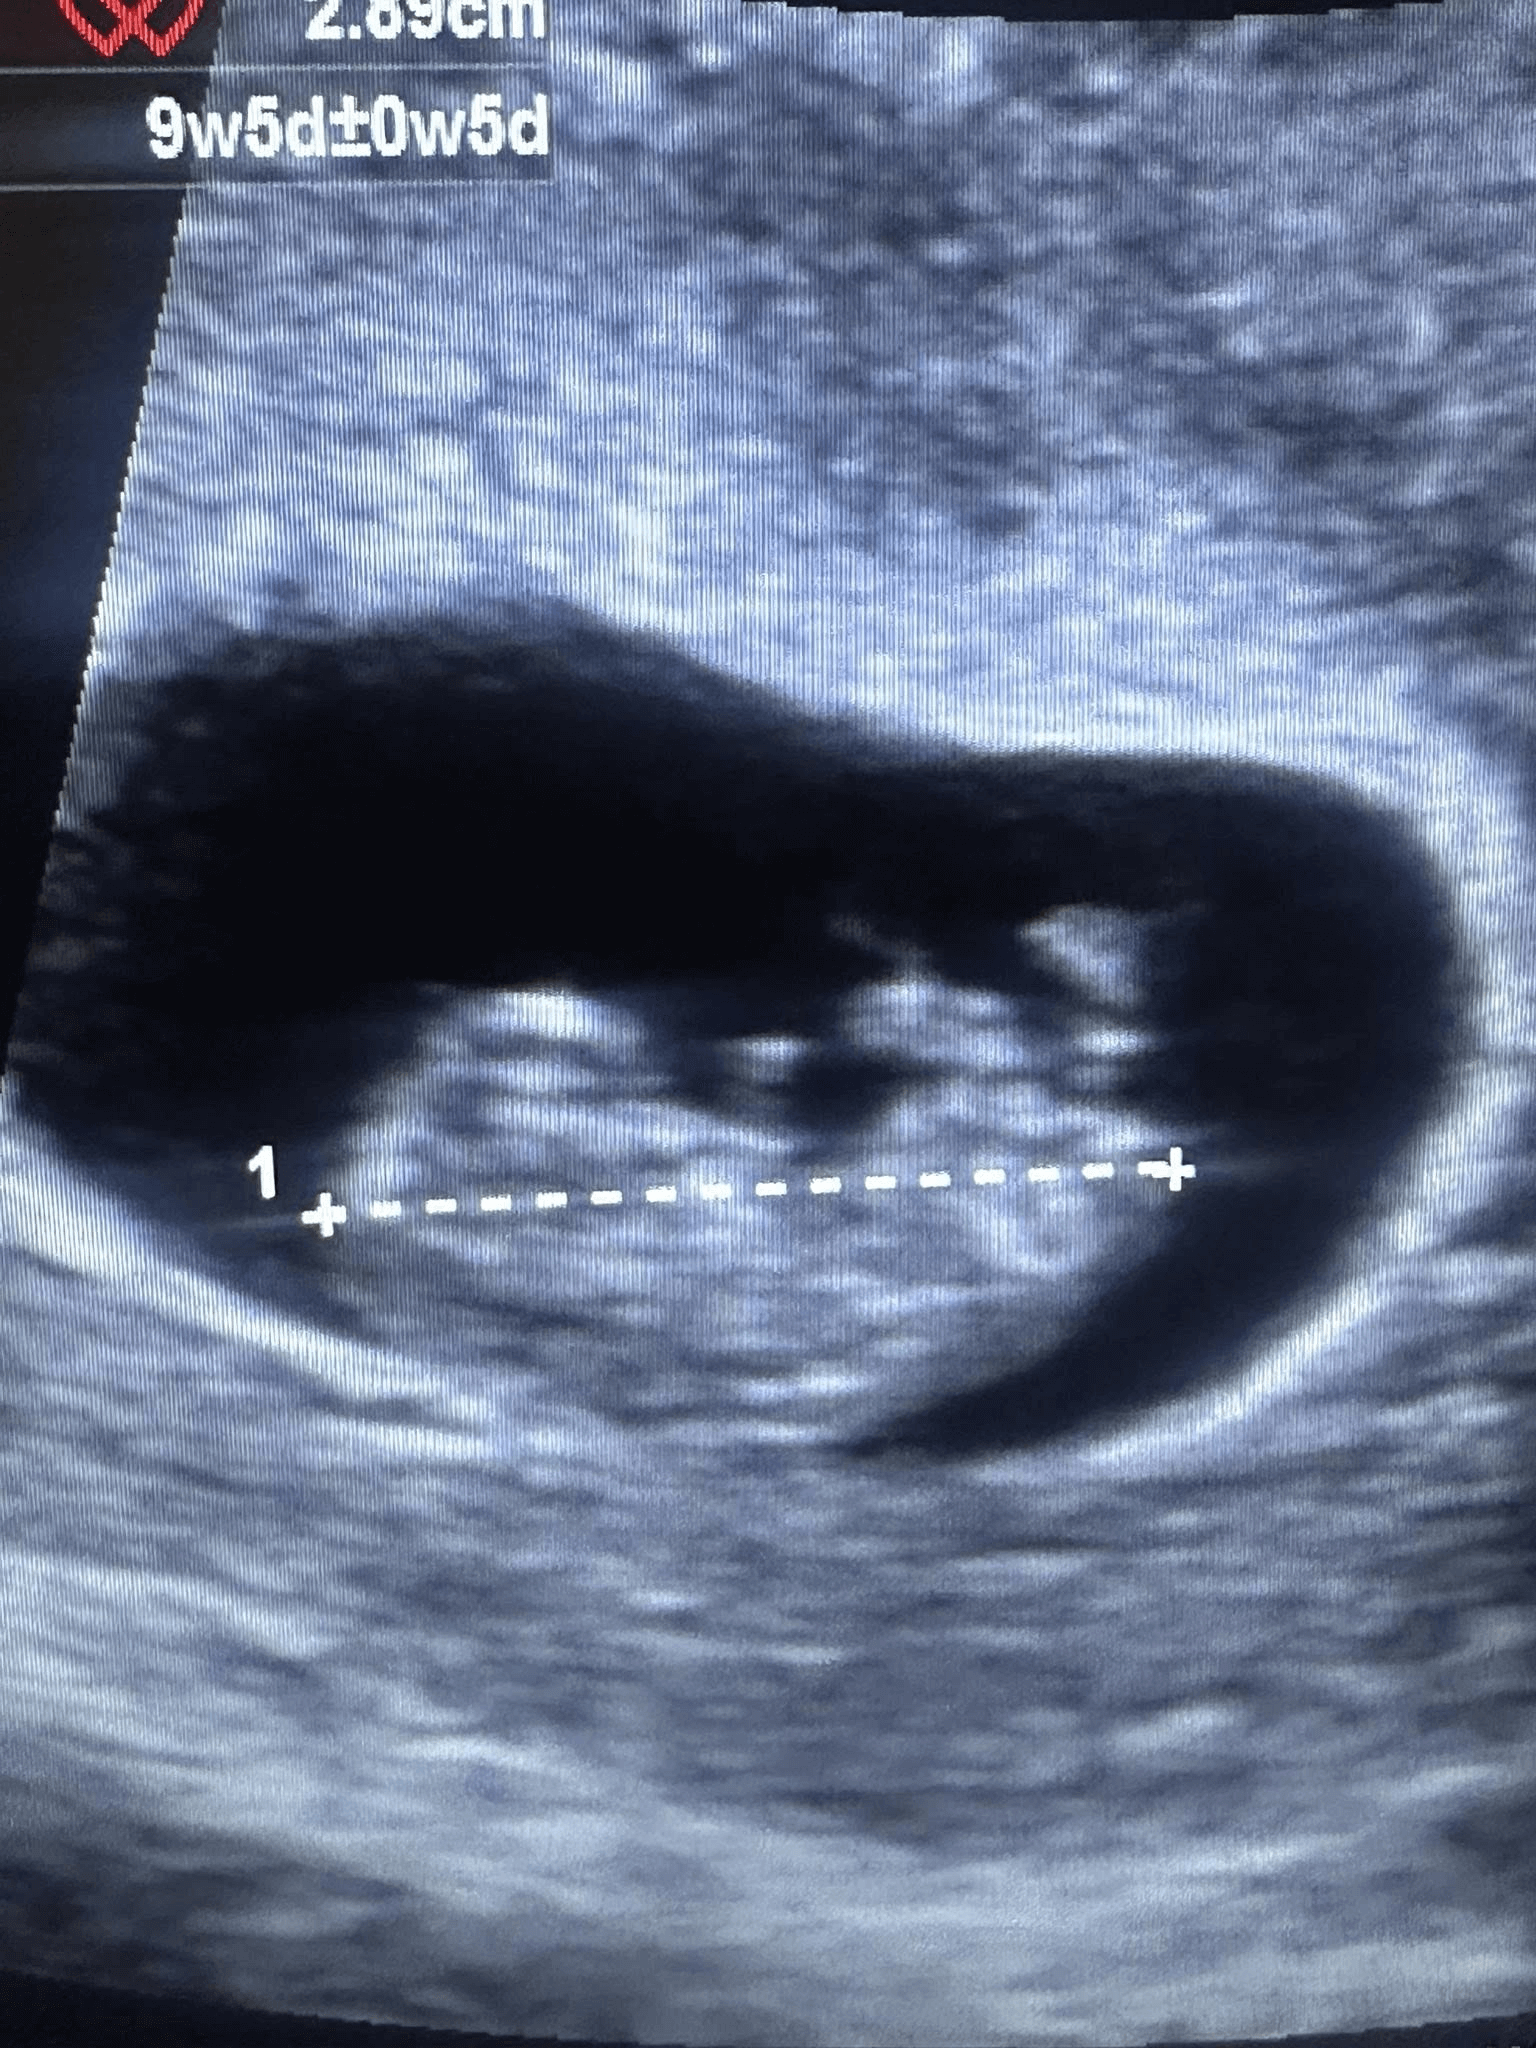

“As these medical professionals image life and introduce moms to their babies for the very first time, they provide valuable information to those who are making life or death decisions - choices that will impact them in every way possible,” she said.

LAUC offers personalized instruction with human models of various gestational ages, computer-generated scans with various pathologies, and scanning with phantom wombs.